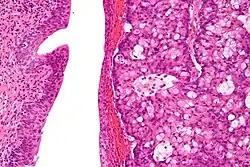

High magnification micrograph of a urachal carcinoma. H&E stain

The urachus is also subject to neoplasia. Urachal adenocarcinoma is histologically similar to adenocarcinoma of the bowel. Rarely, urachus carcinomas can metastasise to other regions of the body, including pelvic bones and the lung.[7]